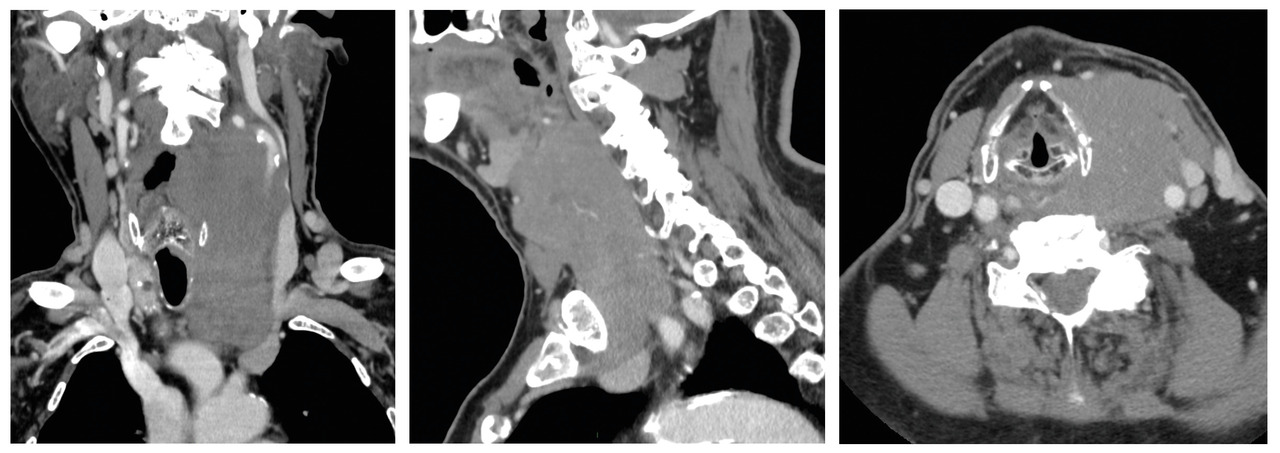

Le nodule peut être découvert à la palpation cervicale par le patient ou son médecin (40 à 50 % des cas), mais, de plus en plus souvent (30 à 40 % des cas),5 il s’agit d’une découverte fortuite lors d’un examen d’imagerie (échographie, scanner [fig. 1], scintigraphie, tomographie par émission de positons [TEP]). Une dysthyroïdie est révélatrice dans 10 à 15 % des cas. Le motif de consultation peut être une gêne fonctionnelle : dysphagie, gêne à la déglutition, dysphonie (si atteinte du nerf récurrent), dyspnée (si compression trachéale) qui peut faire découvrir un goitre thyroïdien (fig. 2). Des signes d’hyperthyroïdie doivent bien évidemment attirer l’attention (nodule toxique, maladie de Basedow).